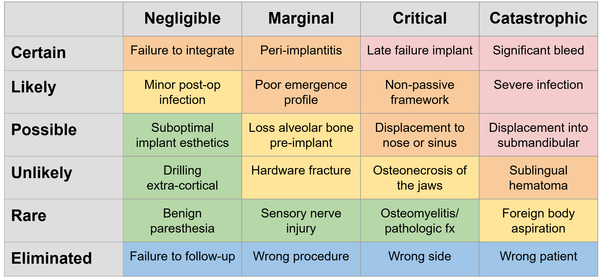

Deep Dive: Updated Guidelines on Implant Placement and Medication-Related Osteonecrosis of the Jaw (MRONJ)

As an oral surgeon, I’m seeing more patients than ever on antiresorptive medications, primarily for osteoporosis or cancer-related bone conditions. In Canada alone, over 2 million people are affected by osteoporosis, with many receiving bone-sparing therapies such as bisphosphonates and denosumab (CMAJ). This prevalence underscores the importance of understanding